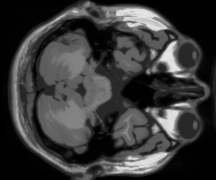

IV-C MRI dataset

In this subsection, an MRI dataset of size is chosen to test our model. Except for the 30 bands used for the test, we select another 10 bands from the raw data as the dictionary training set. And different from the color image experiments, the dictionary used in this part is of size for working well in most situations.

Color images own three channels only, while MRI data often include dozen or hundred bands. In this way, the relationship among different bands will be closer, which is very advantageous to the TNN-based method. However, our SNN-based model still shows its superiority after introducing the CSC prior. The same as color images, we randomly pick 10%, 20%, and 30% samples as the observations, and the results are shown in Fig. 6. It’s intuitive that LRTC-CSC models achieve the best performance among these models, while HaLRTC achieves the worst performance, which verified the effectiveness of CSC regularization. In particular, LRTC-CSC models work well on detailed recovery comparing to TNN-3DTV and Framelet-TV. When the missing rate reaches 90%, our model can still hold a relatively clear result.

Fig. 8 further shows the recovery performance in every band. Both the PSNR and SSIM values of each band show the superiority of LRTC-CSC models. Note that TNN-3DTV can achieve a high SSIM value approaching LRTC-CSC. However, there is a gap between them on the edge band of the whole MRI data. The proposed model LRTC-CSC-I achieves a performance promotion of and with respect to PSNR and SSIM over the results of TNN-3DTV. Moreover, the performances of LRTC-TNN and LRTC-CSC-II on edge band are similar to TNN-3DTV, which implies the shortcoming of TNN-based methods. In other words, TNN can not handle the edge information due to lacking enough neighbors, which is determined by its predominant characteristic of global information capturing. The peformance of TT rank-based method is not satisfactory in MRI data recovering experiments because of imposing KA on the unbalanced tensor [48][49].